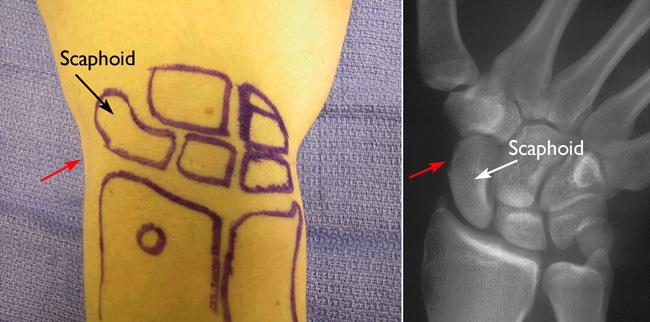

Location of the scaphoid in wrist

Photograph and X-ray showing the location of the scaphoid in the wrist. The red arrows indicate the location of the anatomic snuffbox.